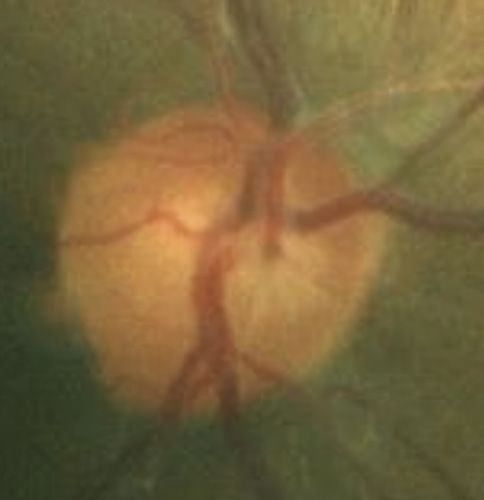

Bild 7: Fall 2 – (a) Sehnervenkopf OD, (b) Sehnervenkopf OS

A 46-year-old African American male presents for glaucoma quarterly monitoring. Medical history is positive for hypertension controlled with 50 mg hydrochlorothiazide and reports no diagnosis of diabetes mellitus or known drug allergies. Ocular history is positive for progressive myopia bilaterally and pigment dispersion syndrome converting to pigmentary glaucoma right eye mild, left eye moderate with treatment initiated in September of 2016. The pigmentary glaucoma was treated with 0.005% latanoprost in both eyes every evening. There was positive family history of glaucoma (patient’s father). Best corrected visual acuity was measured at 20/25 in each eye. Pupillary assessment revealed a stable 1+ afferent pupillary defect in the left eye. Confrontation fields were full to finger count in the right eye and superonasal constriction in the left eye. Extraocular motilities were full with no restrictions or report of diplopia in both eyes. Slit lamp examination is remarkable for a Krukenberg spindle (Figure 4) bilaterally and a Zentmeyer line (Figure 5) in the left eye. Intraocular pressures at 3:30 pm via GAT measured 18 mmHg right eye, 23 mmHg left eye. Gonioscopy was performed and revealed open angles to ciliary body with a concave iris configuration and 4+ trabecular meshwork pigmentation (Figure 6) and the posterior corneal surface. There was no pigment attached to the anterior lens surface. The highest recorded intraocular pressures prior to treatment were 27 mmHg right eye & 35 mmHg left eye. CCT measured 554 microns in the right eye and 538 microns left eye. Optic nerve head assessment revealed bilateral intact neuroretinal rims with vertical elongation greater in the left eye than the right with inferior neuroretinal rim thinning in the left eye (Figure 7).

CD ratios were estimated horizontally/vertically as 0.4/0.5 right eye, 0.6/0.8 left eye. Repeat testing of 24-2 Humphrey Visual Fields (HVF) (Figure 8) and optic nerve head optical coherence tomography (OCT) (Figure 9) were obtained.